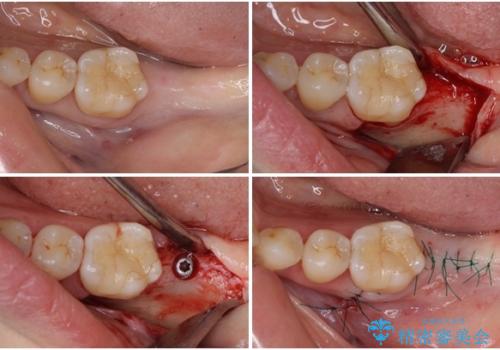

下顎欠損部はインプラントにて、上顎中間欠損部はブリッジによる補綴治療を行い、他にも気になっている銀歯をセラミックインレーやゴールドインレーにて修復治療を行うこととしました。

インプラント治療の注意事項(リスク・副作用など)

- 外科手術のため、術後に痛みや腫れ、違和感を伴います

- メンテナンスを怠ったり喫煙により、お口の中に大きな悪影響を及ぼすインプラント周囲炎等にかかる可能性があります

- 糖尿病、肝硬変、心臓病等の場合、インプラント治療ができない可能性があります

- 高血圧、貧血・不整脈等の場合、インプラント治療後に治癒不全を招く可能性があります

- 自費診療(保険適用外治療)となります